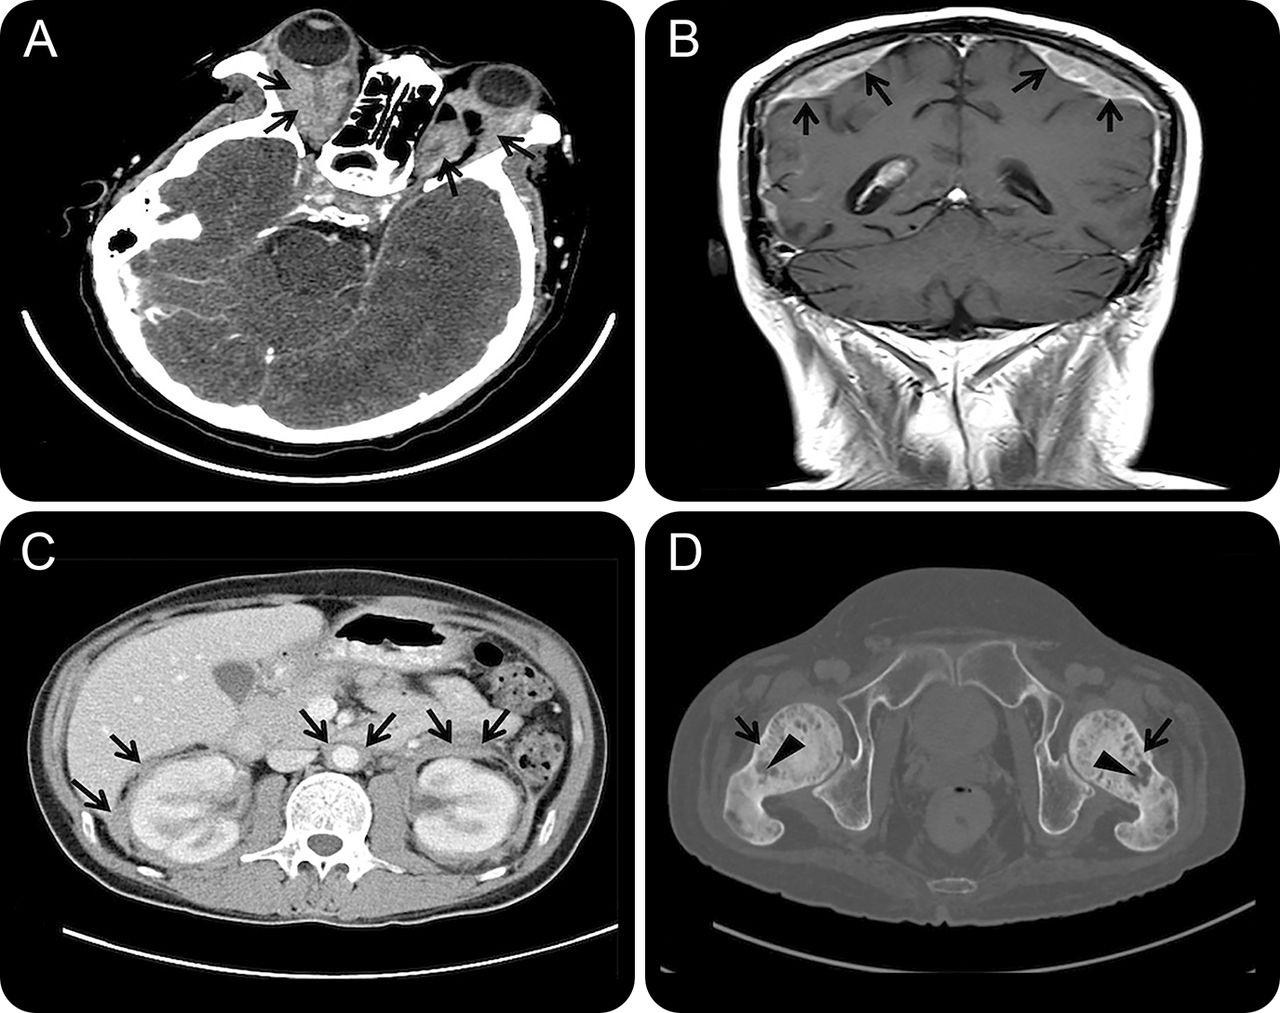

教学神经图片:Erdheim-Chester疾病(polyostotic硬化性组织细胞增生症)

一个34岁的男人面对进步视力丧失,复视,头痛、间歇热,和重要的减肥了7个月。体检显示与完整的眼肌麻痹的双边视力丧失、眼球突出。影像表现pachymeningeal增强,软组织浸润retro-orbital空间和多个器官包括肾脏和腹主动脉,和混合osteosclerotic溶骨的病变在双边股头1(图)。retro-orbital病变的病理研究显示泡沫- CD1a和S1002符合Erdheim-Chester疾病(ECD)。该患者使用静脉甲基强的松龙紧随其后的是环孢霉素以最小的利益。四个月后,他死于不明原因猝死在睡眠中。尸检没有执行。儿童早期开发是一种罕见的non-Langerhans组织细胞增生症,其特点是慢性的多个器官组织细胞的渗透。常见的症状包括骨骼疼痛,尿崩症,眼球突出,黄斑瘤。1神经系统的影响在25% - -50%的患者,可以参与extra-axial intra-axial隔间。1,2标准治疗尚未确定。

图

射线的发现

(一)软组织浸润在双边retro-orbital空间(箭头)。(B)的脑部MRI显示增强pachymeninges(箭头)。(C)腹部CT显示装箱的双边肾脏和主动脉浸润(箭头)。(D)盆腔CT显示混合溶骨的(箭头)和osteosclerotic(箭头)股正面的病变。